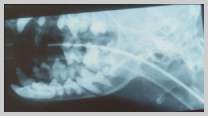

Lateral view of dog with fractured

mandible caudal to symphysis including root tip of canine

tooth